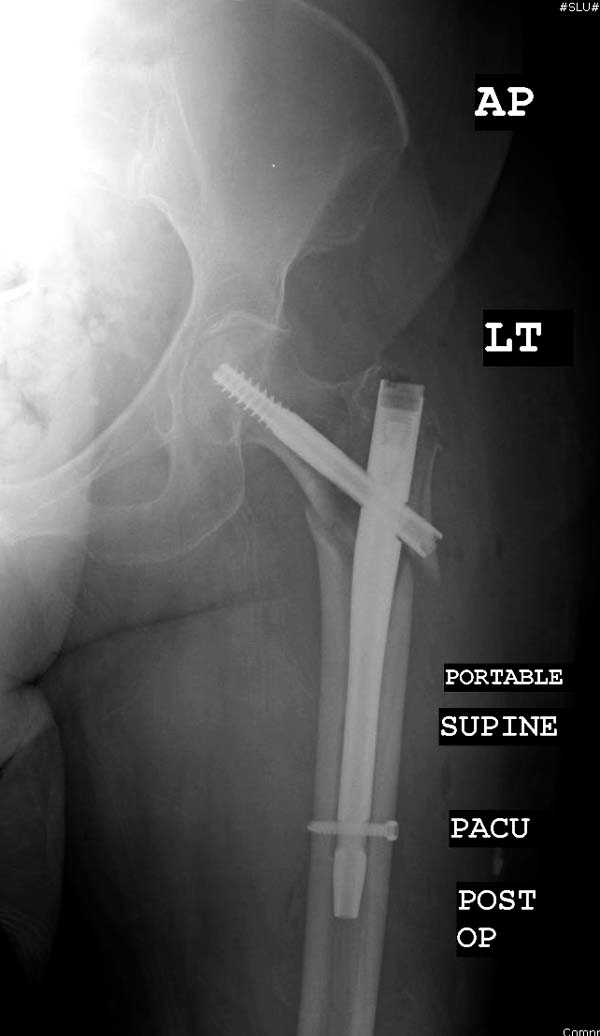

Здесь представлен случай, где в послеоперационном периоде обнаружена техническая ошибка, Gamma 3 установлен с нарушением методики. Больная в 91 лет, прооперирована через день после поступления и выписана через 48 часов.

При первом послеоперационном поликлиническом осмотре больная предъявила жалобы на боли в бедре. В серийных снимках обнаружен продольный перелом верхнего отдела бедра.

Считаем, что техническая ошибка произошла во время установки гвоздя, когда рассверливанию канала не уделили должного внимания. Канал остался узковат, и гвоздь был забит с силой. Полная нагрузка конечности приостановлена на две недели, и боли в конечности изчезли. Больная начала нагрузку и перелом срастается. -- Djoldas Kuldjanov, M.D. Associate Professor Department of Orthopedic Surgery St. Louis University